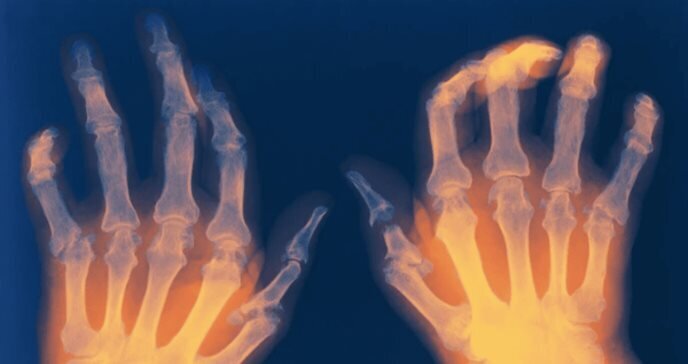

Reumatóloga resalta avances en artritis reumática y menor mortalidad

La reumatóloga del Hospital General Universitario Gregorio Marañón, la doctora Isabel Castrejón, ha destacado que en las últimas décadas se ha observado una disminución mundial de la mortalidad por artritis reumatoide, una situación que achaca a la mejora del uso de los fármacos modificadores de enfermedad (FAME) y un mejor enfoque multidisciplinar, teniendo en cuenta las comorbilidades.

A pesar de ello, la especialista ha recordado que este tipo de pacientes siguen teniendo una mayor mortalidad respecto a la población general, especialmente por las enfermedades cardiovasculares y las infecciones.